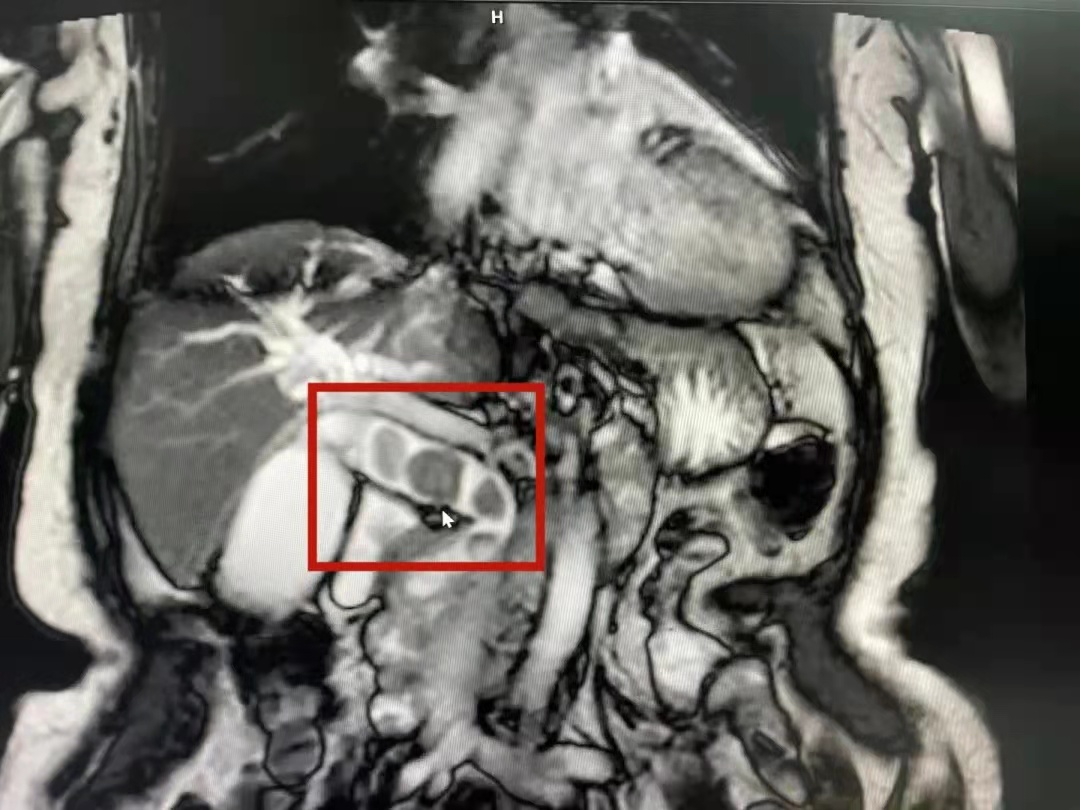

术中所见结石情况

11月15日,有着丰富手术经验的消化内科黄理副主任医师为韦奶奶行ERCP取石术。手术过程中出现了一段“小插曲”,术中发现一憩室,十二指肠乳头内陷于憩室壁内,且里面还有宿食残留挡住了乳头。十二指肠憩室内乳头属于少见的插管困难手术现象,如果处理不当,将会增加术中及术后并发症。黄理副主任医师灵活利用活检钳、圈套器清理宿食后,采取内镜下金属夹牵拉辅助完成胆总管插管,最后依次将三枚结石依次取净,其中最大的结石直径为2.0cm。术后第一天患者的情况好转立竿见影,第二天便可进食流质食物,第三天拔除鼻胆引流管。近日,韦奶奶康复出院。